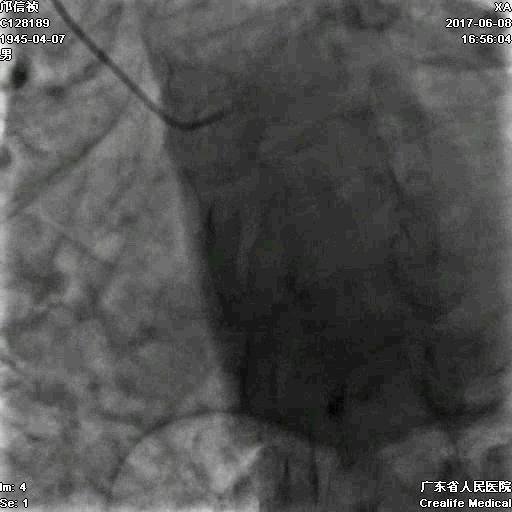

RCA闭塞段球囊扩张后IVUS

支架术后造影结果

支架术后IVUS